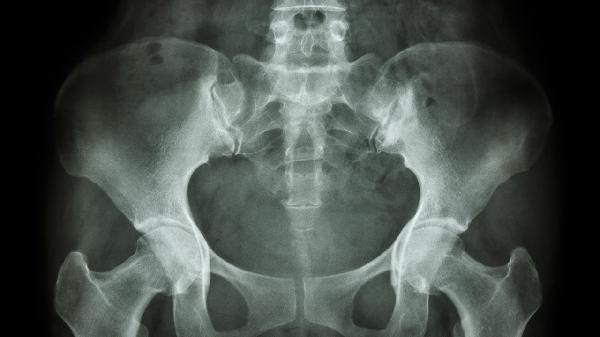

经鼻内镜下切除术适用于中等大小的筛窦骨瘤,具有创伤小、恢复快的优势。手术需完整切除瘤体避免复发,术后可能出现暂时性嗅觉减退,多数在3个月内逐渐恢复。

巨大骨瘤或侵犯颅底时需采用鼻外进路手术,必要时联合神经外科进行颅底重建。该术式能充分暴露病变区域,但可能遗留面部瘢痕,术后需预防脑脊液漏等并发症。